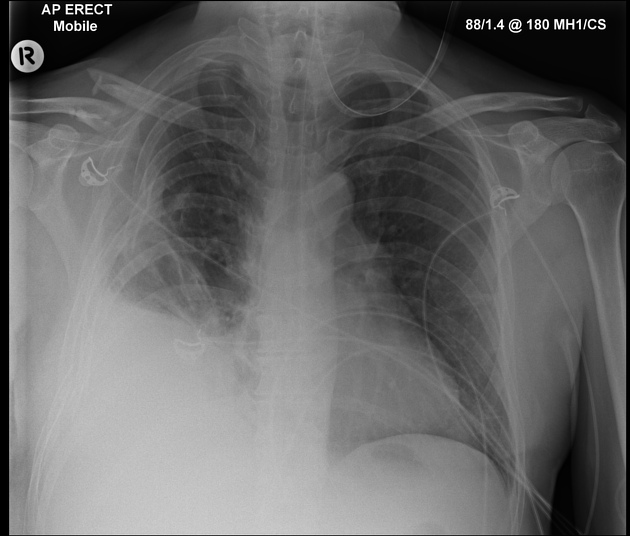

Describe the abnormality demonstrated.

Left-sided pneumothorax and left-sided pleural effusion (costophrenic blunting).